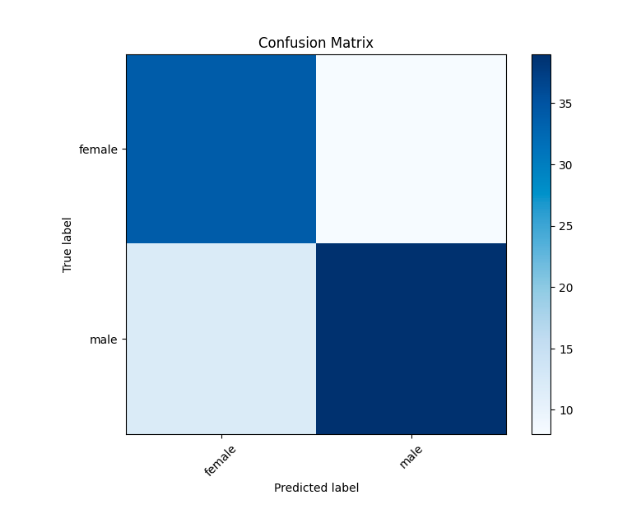

5.4. 模型评估:

训练后,在测试数据集上对模型的性能进行了细致的评估,结果如下。

5.5. 结果:

分类报告: 分类报告提供了两个类别(女性和男性)的详细指标:

分类报告提供了两个类别(女性和男性)的详细指标:

女性:

精度:0.74 召回率:0.81 F1 得分:0.77 支撑:42

雄:

精度:0.83 召回率:0.76 F1 得分:0.80 支撑:51 精度:0.78

宏平均值(精确率/召回率/F1 分数):0.78

加权平均值(精确率/召回率/F1 分数):0.79

这些指标表明模型的性能平衡,总体准确率为 78

实验结果表明,基于胸部X线图像的性别分类卷积神经网络(CNN)模型取得了令人满意的性能。女性和男性类别的准确率、召回率和 F1 分数指标都相当高,总体准确率为 78。